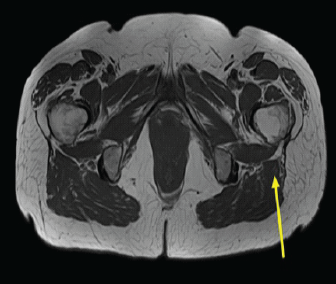

Unusual Presentation of Spinal Osteoid Osteoma: A Case Report

Mehmet Erkilinc

………………………………p.86-89